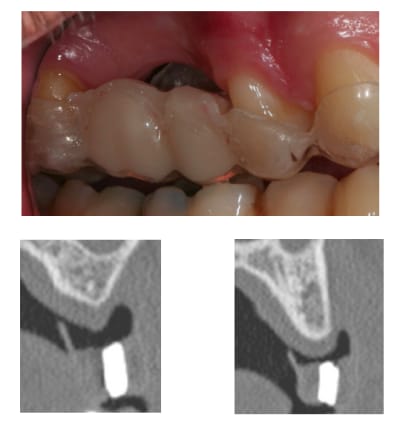

c'est à cause du profil de la crête, en fait l'implant est juxta-osseux en vestibulaire, par contre moi je le trouve ( légèrement ) trop distal.

il est prévu de faire une ROG.

ROG avant implantation ou implantation avec ROG simultanée?

simultanée avec Bio-Oss et os autogène.

et membrane? si oui comment vas-tu la stabiliser?

oui membrane Bio-Gide en double épaisseur, avec rien.

avec Bio-Oss, os autogène et Bio-Gide et pose d'implant simultanée, peut être les photos le mois prochain.